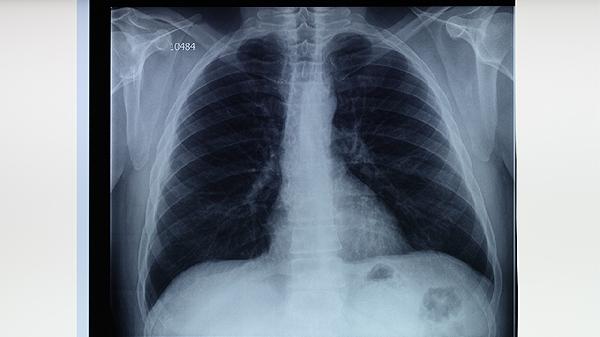

做胸部CT能检查出什么

胸部CT能检出肺部感染、肺结节、胸腔积液、纵隔肿瘤及心血管异常等多种病变。1、肺部感染胸部CT对细菌性肺炎、病毒性肺炎等感染性病变敏感度高,可显示斑片状或磨玻璃......

ct检查肺部有炎症治疗方法有哪些

肺部炎症可通过抗感染药物治疗、糖皮质激素治疗、祛痰治疗、氧疗及生活干预等方式改善,通常由细菌感染、病毒感染、真菌感染、理化因素刺激或自身免疫性疾病等因素引起。建......

ct三维成像是检查什么

CT三维成像主要用于检查人体器官、血管、骨骼的立体结构与病变情况。常见应用主要包括胸部病变定位、骨折精细评估、脑血管畸形筛查、肿瘤体积测量、牙颌骨形态分析等五个领域。1、胸部病变定位CT三维成像能清晰......